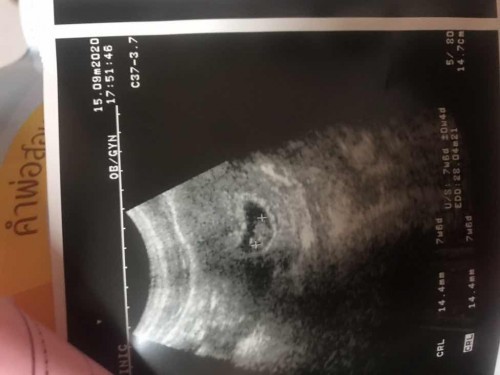

ท้องแรก7วีค6วัน

แบบนี้ความยาวเท่าไหร่ น้ำหนักเท่าไหร่หรอค่ะ

ยาว 14.4 มม. ค่ะ น้ำหนักไม่เห็นค่ะ